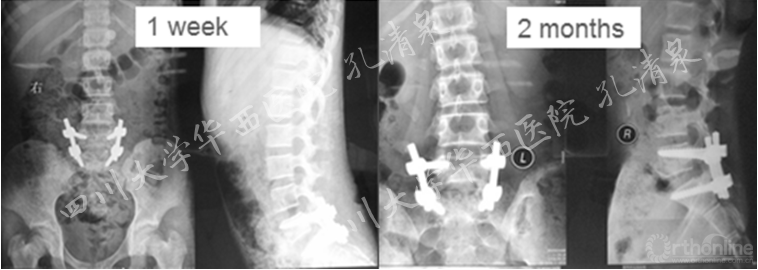

图9 术后一周复查见滑脱复位良好,无侧凸;术后两月复查,复位情况良好,可见轻微腰椎侧凸